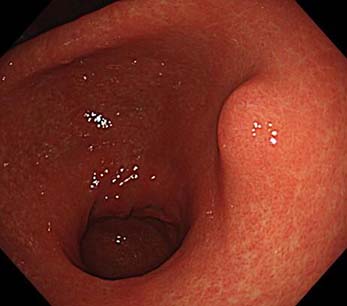

42歳女性。既往歴に特記すべき事項はなく、喫煙歴およびPPI使用歴もない。母方の叔父に胃ポリポーシスの既往がある。自身も胃ポリポーシスを指摘され、精査目的で当院を受診した。

上部消化管内視鏡検査では、胃体部に無数のポリープを認めた。また、体部大弯に15mm大の白色調領域(黄色矢頭)を認めた。生検の結果、ポリープは胃底腺ポリープ、白色部位はtub1であった。十二指腸および大腸にはポリープを認めず、血清ピロリ抗体も陰性であった。

GAPPS(gastric adenocarcinoma and proximal polyposis of the stomach)が疑われたため、遺伝カウンセリングを行った上で遺伝子検査を施行した。その結果、APC遺伝子のexon1Bに病的バリアントが検出され、GAPPSと確定診断された。

本疾患は、常染色体優性遺伝形式をとり、胃近位部に多数の胃底腺ポリープを形成する稀な疾患であり、これらのポリープは腺腫や腺癌への進展をきたすことがある。また、FAP(家族性大腸腺腫症)と異なり、十二指腸および大腸に多発する腺腫を認めないことが特徴である。

本症例では胃癌に対してESDが行われたが、GAPPSは新たな多発胃癌のリスクがあるため、根治治療として胃全摘が推奨される。患者の希望により胃全摘は実施されず、現在は定期的な内視鏡フォローアップを継続している。(New England Journal of Medicine に本症例が掲載されました!Tanaka K, Hirasawa T. Gastric Adenocarcinoma and Proximal Polyposis of the Stomach. N Engl J Med. 2025 Mar 13;392(11):e29.)